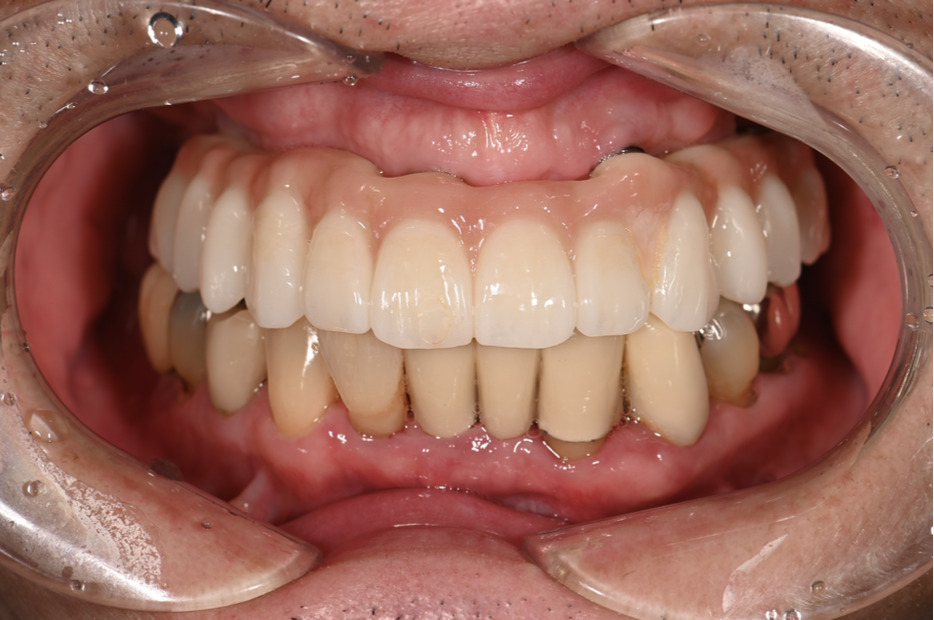

| 主訴 | 全体的にきれいにしたい |

|---|---|

| 治療内容 | 午前中に上下顎共に重度の歯周病、虫歯のため全ての歯を抜歯させていただき下顎はインプラントの土台を3本埋入し歯型を取り午後に上部構造(下顎全ての歯)を装着、上顎は一度総入れ歯を装着させていただきました。 治療が1日で完了しその日のうちに噛めるようになります。 |

| 治療期間 | 2回(1回目に資料取りをさせていただき2回目に下記の全ての治療をさせていただきました。) |

| 治療費 | 250万円 |

| 治療 リスク | 抜歯した部位などに関しては当日痛みが出ますので痛み止めなどを処方させていただきます |